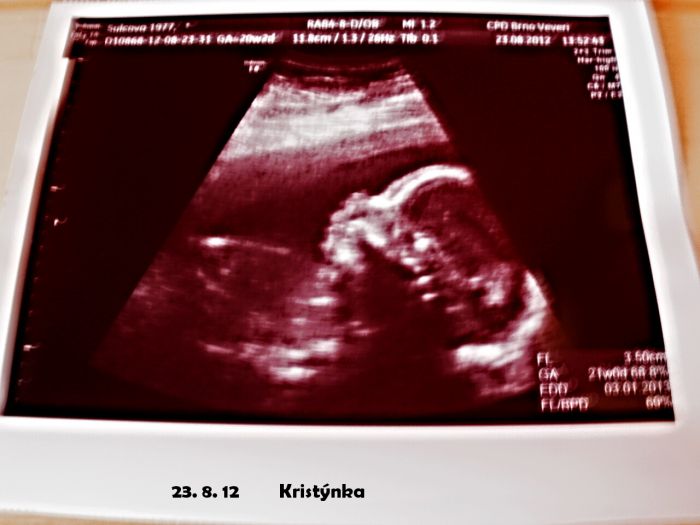

Ahoj, krásný fotečky. Tak přidávám taky jednu

Jana: Jéé to je krásný snímeček, vážně krásné :)